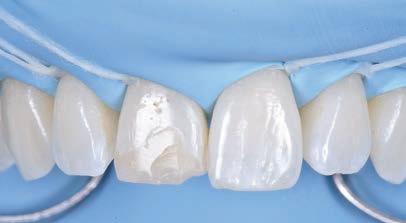

5: A treatment mock-up may be fabricated in a flexible machinable polycarbonate based on the contours of a final proposed restoration, in such a manner as to be capable of fitting to the contours of the pre-operative situation.

At the laboratory, the dental technician may merge these digitised records using Zirkonzahn.Modifier software (Zirkonzahn Srl; Gais, Italy) to form a precise 3D rendering of the patient’s pre-operative dentofacial situation, with all biomechanical and aesthetic landmarks conveniently available for reference. This offers the technician unparalleled, high-fidelity access to key diagnostic clinical information when compared to conventional analogue-based workflows.4 At this stage, an end goal of prosthodontic treatment may be developed wherein the contours of the proposed restorations are informed on the basis of the patient’s physiognomy, or rather, their unique and characteristic facial features (Figure 4).9 The final proposed design may be fabricated into a snap-on smile try-in, or treatment mock-up, using a flexible machinable polycarbonate (Temp Premium Flexible; Zirkonzahn Srl, Gais, Italy) (Figure 5).

At this early stage of diagnostic work-up, prior to any operative intervention, the clinician and the technician can now communicate to each other and, most importantly, to the patient, in an understandable visual rhetoric, a precise end goal of treatment from which a meeting of the minds may be achieved (Figures 6 and 7).5